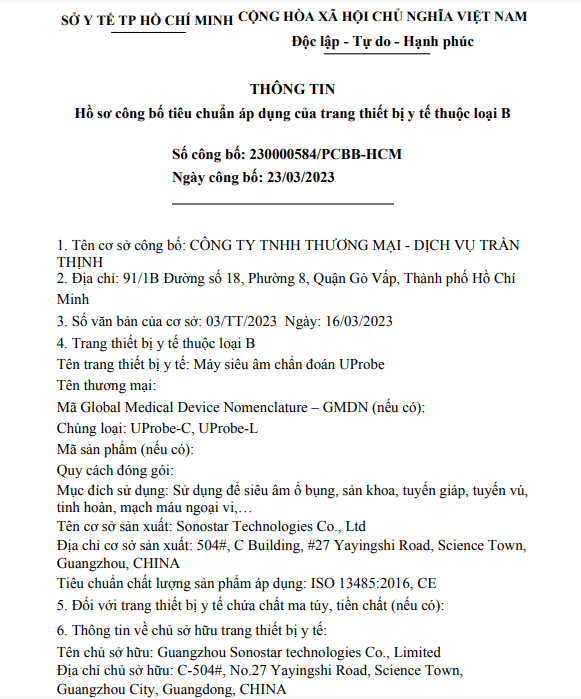

At the Spanish Medical Academic Conference, SonoStar portable color Doppler ultrasound has become a

At the Spanish Medical Academic Conference, SonoStar portable color Doppler ultrasound has become aVIEW MORE →2026-02-10 -